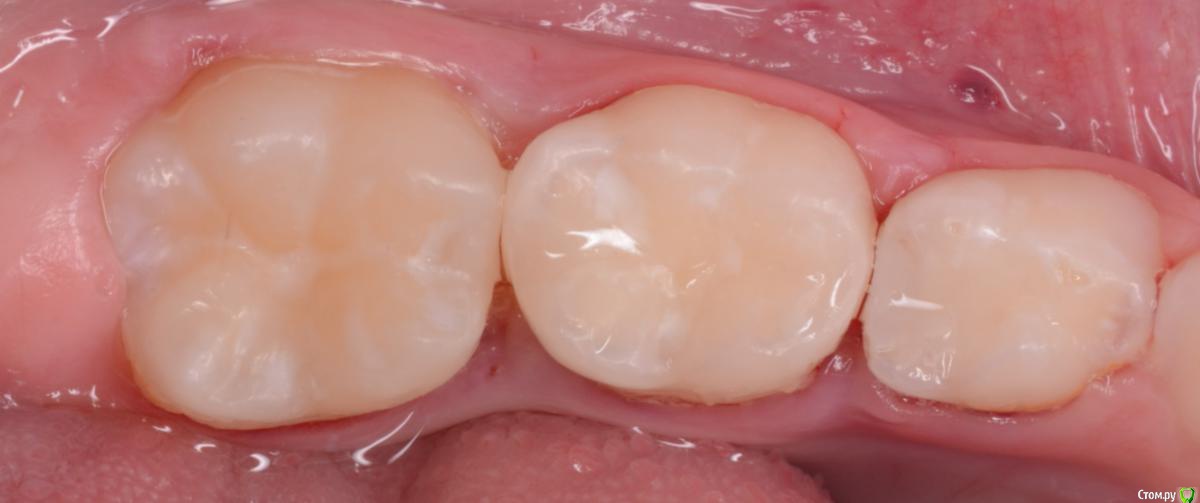

CRAZYDUCK Опубликовано 20 февраля, 2020 Автор Поделиться Опубликовано 20 февраля, 2020 Верхнее фото - зуб с герметиком . Со слов мамы перед герметизацией зуб не чистили , врач сразу нанёс герметик ( по виду похоже на жидкотекучий композит ).под жидкотекучим был кариес . Убрала жидкотекучий композит рондофлекс , препарирование и восстановление пакуемым и герметиком . 2 Ссылка на комментарий

CRAZYDUCK Опубликовано 21 февраля, 2020 Автор Поделиться Опубликовано 21 февраля, 2020 Почему-то не по порядку фото грузятся . Ребёнок 4 года , ранее был опыт лечения в наркозе , 7.5 восстановлен окклюзионно и вестибулярно , 7.4 окклюзионно . На фото «до» видно налёт в пришеечной зоне . Восстановила коронками в ЗакС 1 Ссылка на комментарий